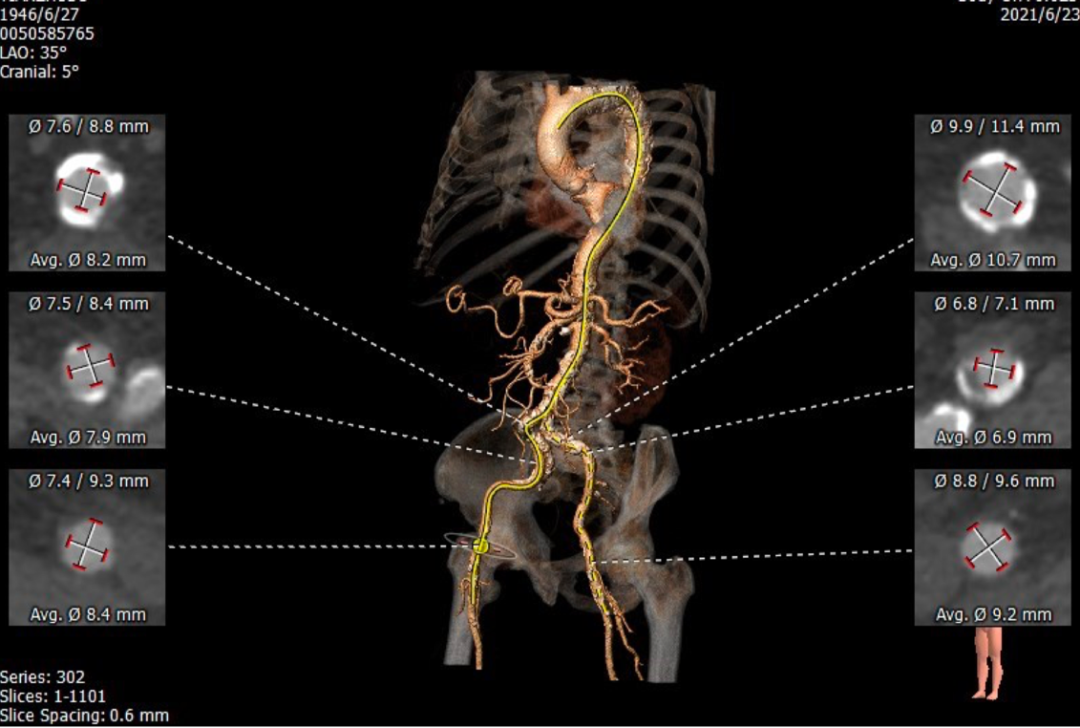

CT提示为该患者三叶瓣,右无轻度融合,冠脉开口高度尚可,窦部空间可,髂总动脉近环形钙化,内径可,计划予以23mm球囊扩张,植入Venus A 26瓣膜。